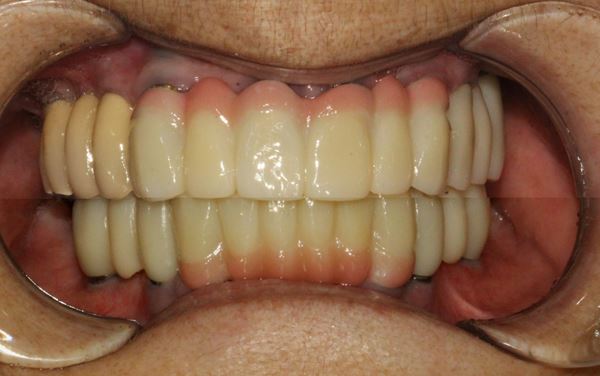

전체 보철물 세팅

6개월 정도 지난 후 임플란트 보철 세팅

보철이 없는 동안은 임시 의치(틀니)를 사용함

앞니의 경우 잇몸이 내려가서 치아 길이가 길어보일 수 있기 때문에 보철 부분에 잇몸 색상을 넣어서 자연스럽게 하였습니다.